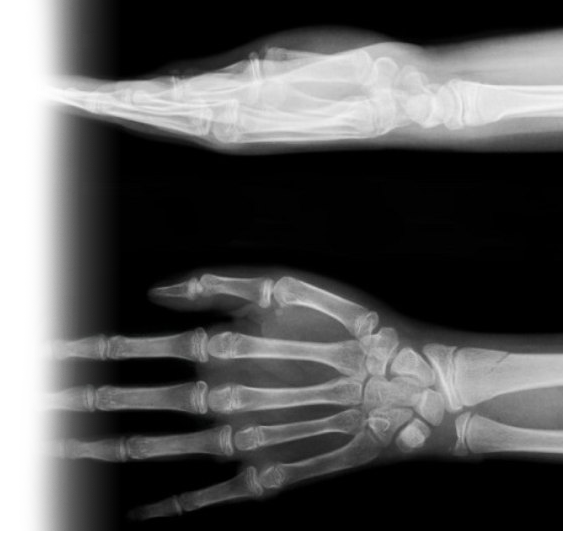

Рентгенография кисти – важный метод прицельного исследования, который позволяет оценить состояние внутренних структур кисти.

Данные исследования позволяют исключить патологию запястья и пальцев кисти ревматологического, костно-травматического, дегенеративно-дистрофического генеза.

Показания для проведения рентгена кисти:

• травма, боль, отек в области запястья;

• травма, боль, отек в области кисти;

• травма, боль, отек в области пальцев кисти.